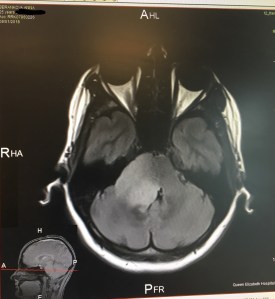

Another reason why I decided to “let my tumour be” is due to the very nature of my diagnosis. I’m very lucky as my lesion is so far (knock on the wood) low-grade. But because of its shape (diffuse intrinsic) and location (brainstem), it cannot be operated. The surgery would be very risky and impossible to remove everything. To illustrate, just getting to the brainstem (before even starting the incision) would take a neurosurgeon 4 hours.

So yeah… I don’t have many options. I always knew that but it only truly dawned on me recently. I had three MRI scans in the last 4 months and the conclusion is that my tumour has progressed by 5mm since 2016. This outcome is not a disaster but it is not a great news.